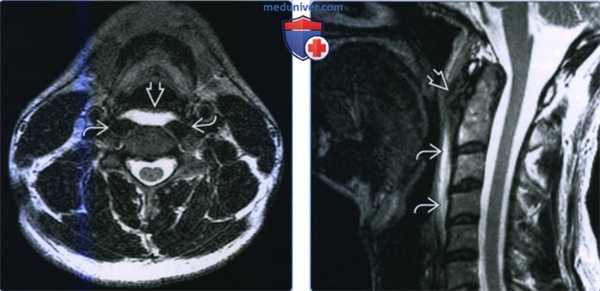

(Слева) КТ с КУ, аксиальный срез, костное окно. В предпозвоночном пространстве визуализируются неоднородные участки кальцификации, по центру и слева. Кальцификаты располагаются в области дуги первого шейного позвонка, в месте, где расположено сухожилие длинной мышцы шеи.

(Справа) МРТ Т1ВИ FS с КУ. Участки выпадения сигнала представляют собой кальцификаты. Контраст накапливается в длинной мышце шеи, а также в заглоточном пространстве, что говорит об имеющихся воспалительных изменениях.

(Слева) МРТ Т2ВИ в аксиальной проекции, выраженный отек заглоточного пространства на фоне тендинита сухожилия длинной мышцы шеи. Жидкость расположена кпереди от предпозвоночных мышц и кзади от слизистого пространства глотки.

(Справа) МРТ Т2, сагиттальная проекция. Участок гипоинтенсивного сигнала в области сухожилия длинной мышцы шеи, на уровне второго шейного позвонка, который представляет собой кальцификаты. Предпозвоночные и заглоточные мягкие ткани отечные, на Т2ВИ имеют гиперинтенсивный сигнал. Изменения в области межпозвоночных суставов, характерные для спондилодисцита, отсутствуют.